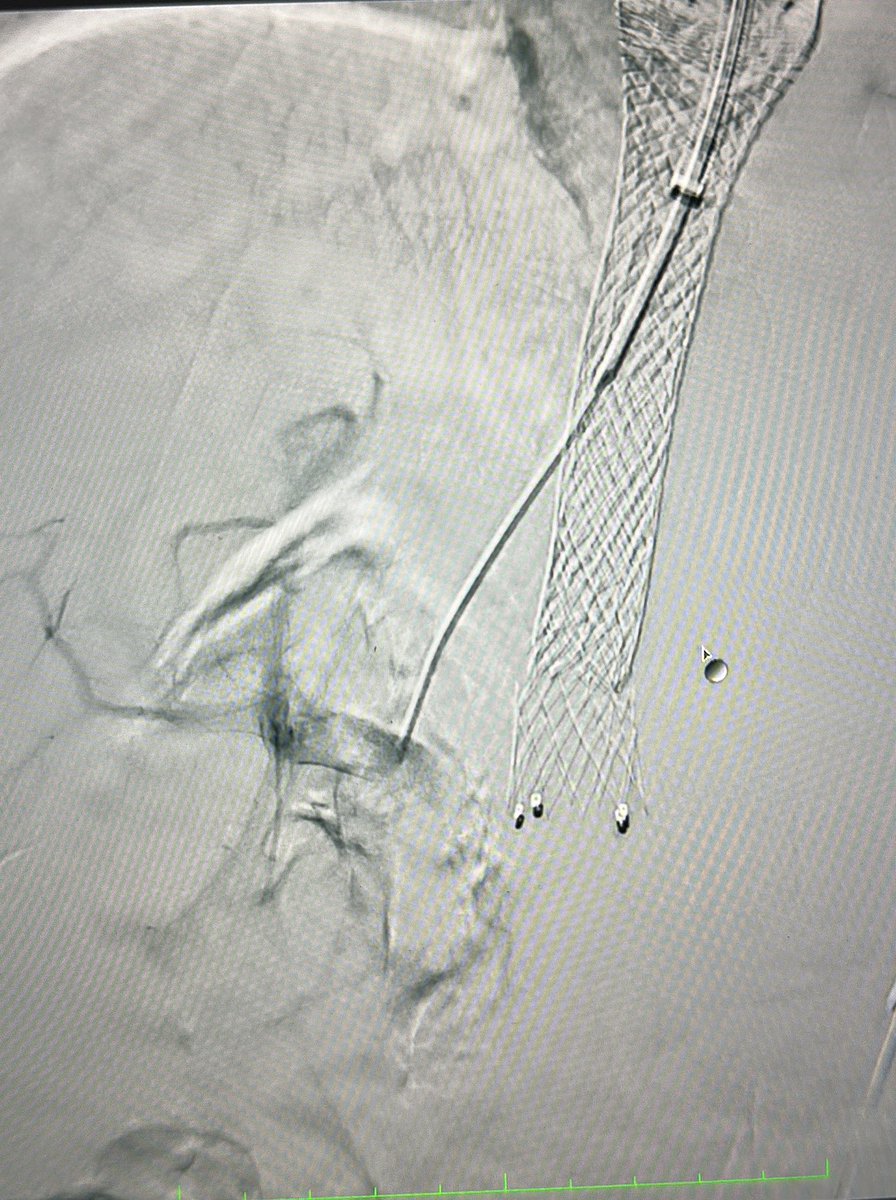

Case 47: with @BhaveshPopat7

CLI; great toe wound; long seg CTO ATA & PTA; antegrade crossing 4fr support cath + progreat and fielder combo f/b plasty 2.5mm; images 👇

#irad #MedEd #CardioTwitter #MedTwitter #radres @SIRRFS @SIR_ECS @CLIfighters @Vascupedia_com @VascularForum